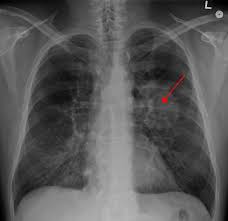

What Are Symptoms Of Advanced Lung Cancer - Surprising Lung Cancer Symptoms / Lung cancer won't wait for the pandemic to be over, so, as well as a persistent cough, it is critical that as many people as possible are aware of other less commonly known symptoms of the disease.. Cancer cachexia, a syndrome including unintentional weight loss and muscle wasting, is very common in the later stages of cancer. Signs and symptoms of lung cancer may include: Persistent coughing, coughing up blood or excess mucus, shortness of breath, and chest pain are all common signs of lung cancer. Treating symptoms of advanced lung cancer. As other parts of the body are affected, new lung cancer symptoms may develop, including:

As other parts of the body are affected, new lung cancer symptoms may develop, including: Advanced stages of lung cancer are often characterized by the spread of the cancer to distant sites in the body. Symptoms to know about stage 4 lung cancer. Cancer treatments also often have side effects. Treatments such as chemotherapy, radiotherapy or targeted cancer drugs can help to shrink the cancer, reduce symptoms and help you feel better.

A new cough that doesn't go away coughing up blood, even a small amount Managing symptoms of advanced cancer while advanced cancer cannot be cured, there are still things that can be done to help you feel as good as possible for as long as possible. Weight loss is also almost universal, and it occurs even when people are eating a diet with adequate calories. A tumor can block the airway, causing a cough or shortness of breath. The most common symptoms of lung cancer are: Here are five symptoms of lung cancer that you might not be aware of: Little is known on symptom burden, psychosocial needs, and perception of prognosis in advanced lung cancer patients at the time of diagnosis, although early assessment is strongly recommended within the setting of daily routine care. Or, hormones released by the tumor can cause carcinoid syndrome (see below). Lung cancer won't wait for the pandemic to be over, so, as well as a persistent cough, it is critical that as many people as possible are aware of other less commonly known symptoms of the disease. Cancer cachexia, a syndrome including unintentional weight loss and muscle wasting, is very common in the later stages of cancer. Feeling increasingly out of breath is a common symptom of advanced lung cancer, according to the british lung foundation. They lose weight a lot, as nutrition in case of lung cancer is poor due to lack of appetite. People with lung cancer often experience signs and symptoms of the cancer, as well as side effects of treatment.

Bone pain or fractures if it's spread to your bones headaches, vision issues, or seizures if it's. The presence of these symptoms doesn't definitively mean you have lung cancer, though, as they can also be caused by other conditions. Signs and symptoms of lung cancer typically occur when the disease is advanced. Persistent coughing, coughing up blood or excess mucus, shortness of breath, and chest pain are all common signs of lung cancer. But doctors and nurses can offer support and treatment to help you.

Management Of Locally Advanced Non Small Cell Lung Cancer N 120 Download Table from www.researchgate.net Persistent coughing, coughing up blood or excess mucus, shortness of breath, and chest pain are all common signs of lung cancer. Little is known on symptom burden, psychosocial needs, and perception of prognosis in advanced lung cancer patients at the time of diagnosis, although early assessment is strongly recommended within the setting of daily routine care. Advanced lung cancer can cause uncomfortable symptoms. Other less frequent symptoms of advanced lung cancer include diarrhea, blackouts, itching, tremor and aches. Of lung cancers are already in advanced stages before doctors find them, according to a 2015 review. Cancer cachexia, a syndrome including unintentional weight loss and muscle wasting, is very common in the later stages of cancer. Cancer may start in one part of the body, but as it advances, it usually spreads. This may affect the bones, liver or brain.

Cancer treatments also often have side effects. A tumor can block the airway, causing a cough or shortness of breath. Signs and symptoms of lung cancer typically occur when the disease is advanced. But doctors and nurses can offer support and treatment to help you. Signs and symptoms of lung cancer may include: Persistent coughing, coughing up blood or excess mucus, shortness of breath, and chest pain are all common signs of lung cancer. If you notice some of these symptoms in your loved one, we recommend contacting their primary care physician and/or hospice care provider immediately: Advanced lung cancer can cause uncomfortable symptoms. A lung net is much less likely to cause carcinoid syndrome than a gi tract net. This may affect the bones, liver or brain. Feeling increasingly out of breath is a common symptom of advanced lung cancer, according to the british lung foundation. Lung cancer is very hard for doctors to find in its early stages. Even if you have symptoms, like a cough or feeling tired, you might not feel bad enough to see a doctor.

Signs and symptoms of lung cancer may include: Lung cancer can spread to: People with lung cancer often experience signs and symptoms of the cancer, as well as side effects of treatment. Lung cancer is the most common cancer as well as the most frequent cause of cancer death in the world today world health organization, 2013.despite advances in the detection, pathological diagnosis and therapeutics of lung cancer, many patients still develop advanced, incurable and progressively fatal disease. Symptom management is one of the critical parts of care for patients with advanced disease.

Here are five symptoms of lung cancer that you might not be aware of: Cancer treatments also often have side effects. Immunotherapy treatments are generally reserved for people with locally advanced lung cancers and cancers that have spread to other parts of the body. The presence of these symptoms doesn't definitively mean you have lung cancer, though, as they can also be caused by other conditions. Lung cancer won't wait for the pandemic to be over, so, as well as a persistent cough, it is critical that as many people as possible are aware of other less commonly known symptoms of the disease. Symptoms of lung cancer at stage 4. When you hear someone speaking about stage i (1), stage ii (2) lung cancer, etc., that is a statement of how much cancer has spread past the lungs. Other symptoms of advanced cancer depend on where the cancer is in the body. Symptoms of metastatic lung cancer that has spread to other parts of the body may include: The lymph nodes within the chest, or in the tummy (abdomen), neck, or armpit Headaches, weakness or numbness in a limb, dizziness, balance issues or seizures (if the cancer has spread to the brain) jaundice (if the cancer has spread to the liver) pain in the bones of the back or hips Because lung cancer develops in the lungs, as you'd probably expect, its most common symptoms involve the lungs. The acs recommend seeking consultation if the following symptoms become apparent: